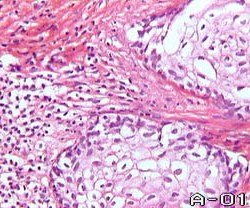

Плоскоклеточный рак всегда является метапластической опухолью по отношению к злокачественным новообразования предстательной железы. Источником его развития могут быть метаплазированные эпителиоциты ацинарных или протоковых отделов предстательной железы. Прослеживается абсолютная аналогия с аденокарциномой и переходноклеточным раком по определению степени дифференцировки для данной гистогенетической группы. Нарастание степени морфологической анатоплазии (снижение степени дифференцировки), сочетающееся с потерей клетками паренхимы опухоли своих основных морфофункциональных характеристик и увеличением значимости солидного компонента, является основанием для подразделения плоскоклеточного рака на степени дифференцировки.

Плоскоклеточный рак I степени дифференцировки - опухоль, в которой среди атипичных эпителиоцитов многослойного плоского эпителия, обнаруживаются образования в виде так называемых "раковых жемчужин". Они представляют из себя ничто иное как, глыбки кератогиалина (процесс локальной гиперкератинизации) , окруженные атипичными эпителиоцитами. Помимо этого, сохраняющие тенденцию к стратификации клетки паренхимы рака, в подавляющем большинстве, содержат в цитоплазме кератогиалин.

Плоскоклеточный рак I степени дифференцировки - опухоль, в которой среди атипичных эпителиоцитов многослойного плоского эпителия, обнаруживаются образования в виде так называемых "раковых жемчужин". Они представляют из себя ничто иное как, глыбки кератогиалина (процесс локальной гиперкератинизации) , окруженные атипичными эпителиоцитами. Помимо этого, сохраняющие тенденцию к стратификации клетки паренхимы рака, в подавляющем большинстве, содержат в цитоплазме кератогиалин.

Способность к синтезу кератогиалина сохраняется лишь в виде внутриклеточной его конденсации. Встречаются участки солидного строения опухоли.

Плоскоклеточный рак III степени дифференцировки представлен резко атипичными клетками, образующим солидные структуры, в которых лишь на отдельных участках прослеживается тенденция к стратификации. Лишь отдельные эпителиоциты сохраняют способность к внутриклеточному синтезу кератогиалина.